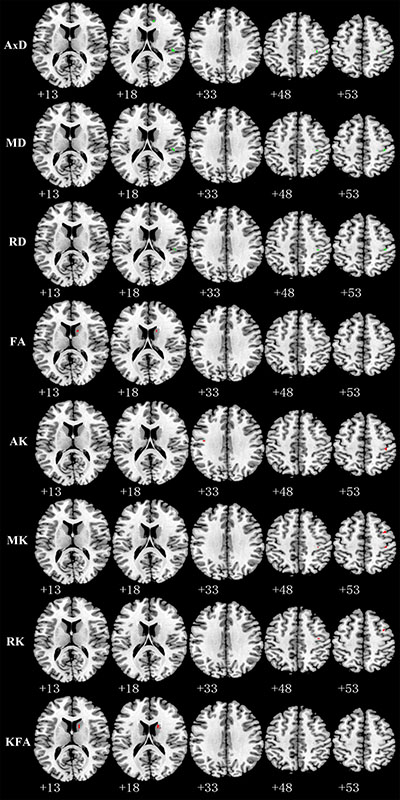

Relative to TT homozygotes, KIBRA C-allele carriers showed increased AxD, MD, RD in right postcentral gyrus and right insula, decreased AK, MK in right postcentral gyrus, as well as decreased FA (fractional anisotropy), KFA in right caudate head (Figure 2). The results are listed in Table 3. Moreover, KIBRA C-allele carriers showed increased MK and RK in the left parahippocampus, compared to TT homozygotes (Figure 3). The results are listed in Table 4.

Figure 2: Representative axial images show GM regions differences (p < 0.001,with a minimum cluster size 10) between TT carriers and C carriers for all indices: AxD, MD, RD, FA, AK, MK, RK, and KFA. Green and red represents the clusters with increased and decreased indices in KIBRA C-allele carriers compared with TT carriers, respectively. Abbreviation: AxD: axial diffusivity; MD: mean diffusivity; RD: radial diffusivity; FA: fractional anisotropy; AK: axial kurtosis; MK: mean kurtosis; RK: radial kurtosis; KFA: kurtosis fractional anisotropy.